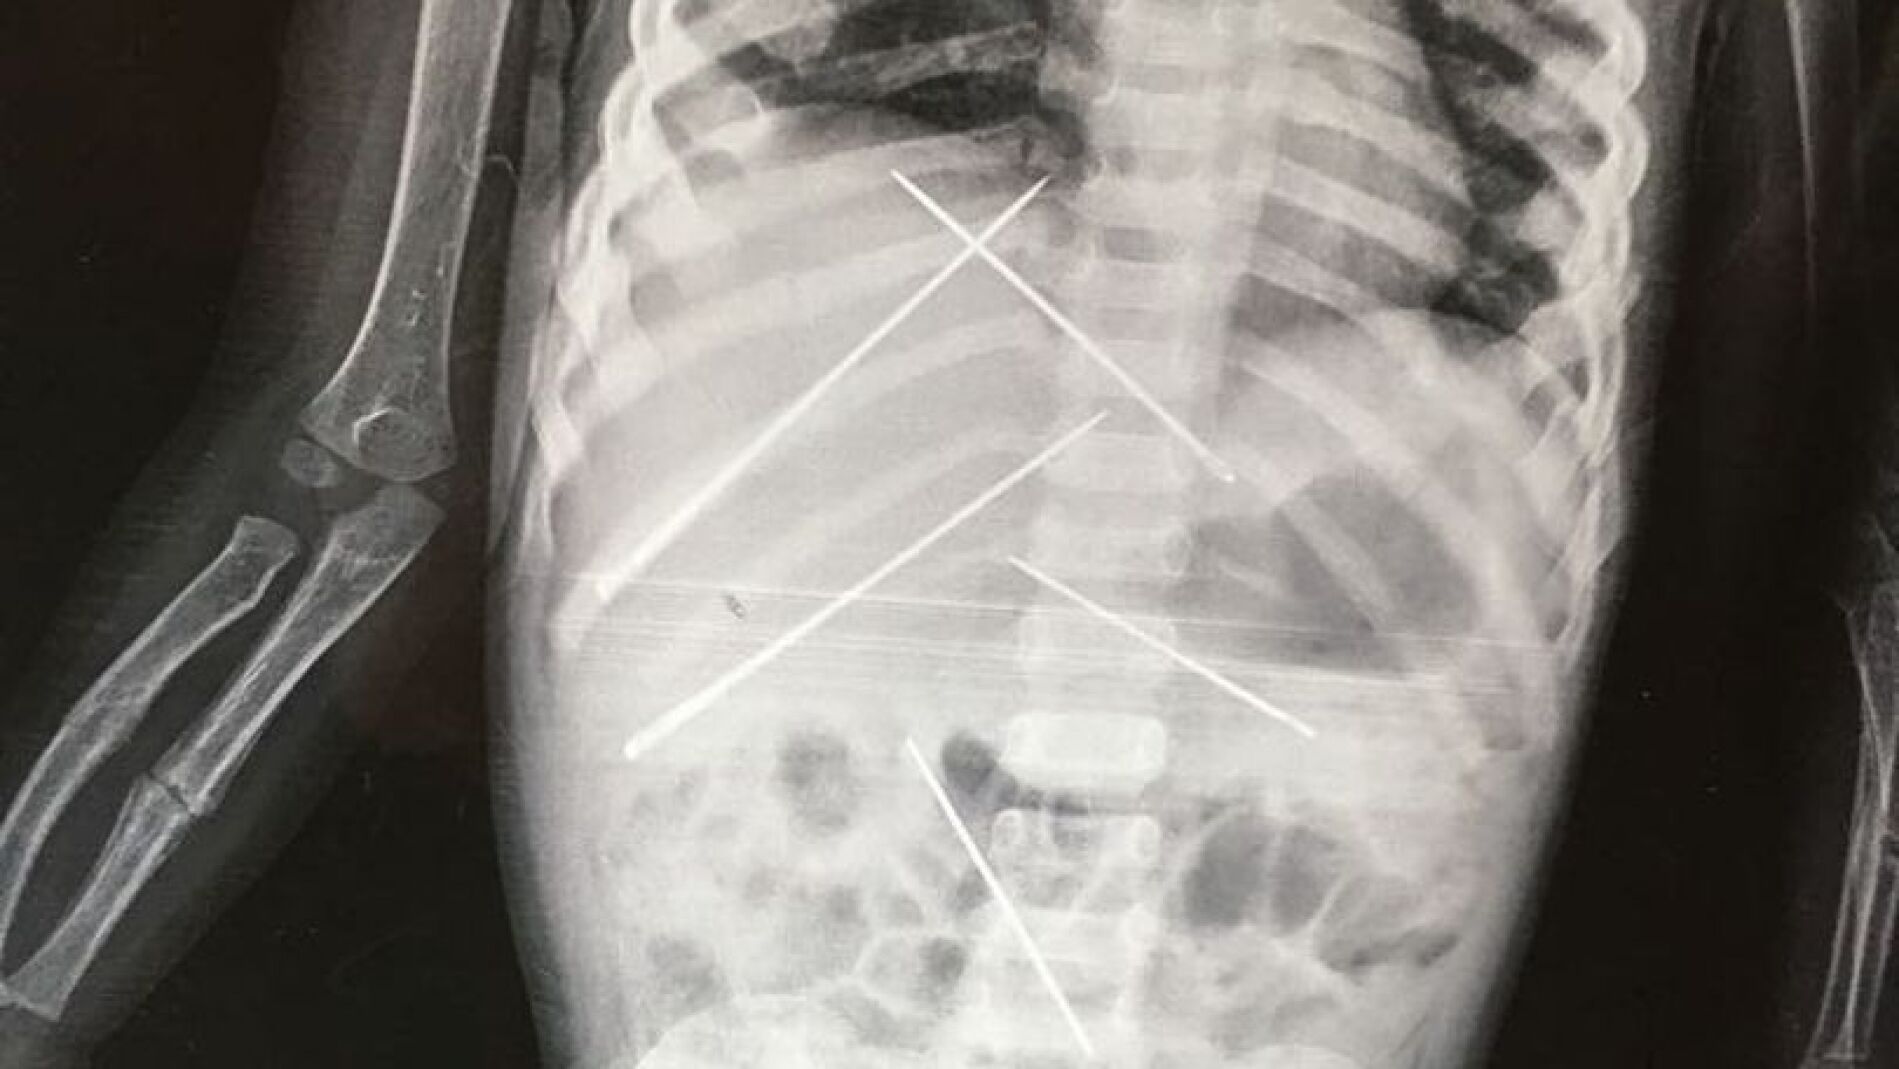

Las radiografías mostraban agujas dentro de su cuerpo que no pudieron ser extraídas por miedo a ocasionar un daño aún mayor. Al parecer, el responsable de los abusos sexuales y de las prácticas de vudú era el jefe de su madre, que la empleaba como trabajadora doméstica.

Una niña de tan sólo tres años ha fallecido a causa de las prácticas de vudú y magia negra que practicaba con ella el jefe de su propia madre, quien, al parecer, le introdujo al menos unas siete agujas dentro de su cuerpo, según informa el diario 'India Today'.